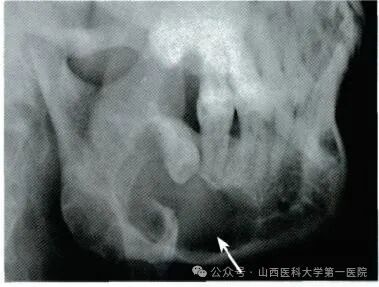

颌骨囊肿多发生在青壮年,可发生在颌骨的任何部位,初期多无自觉症状,增长比较缓慢,可能是牙齿根尖出现的根尖囊肿,也可能是涉及到颌骨的较大囊肿。

早期筛查:成年人的高发人群或易感人群应自觉进行口腔检查,每3-5年一次,进行视诊、触诊、X线片筛查等,其中X线片是一种简单易行且误诊率较低的方法,可以快速定位疾病。